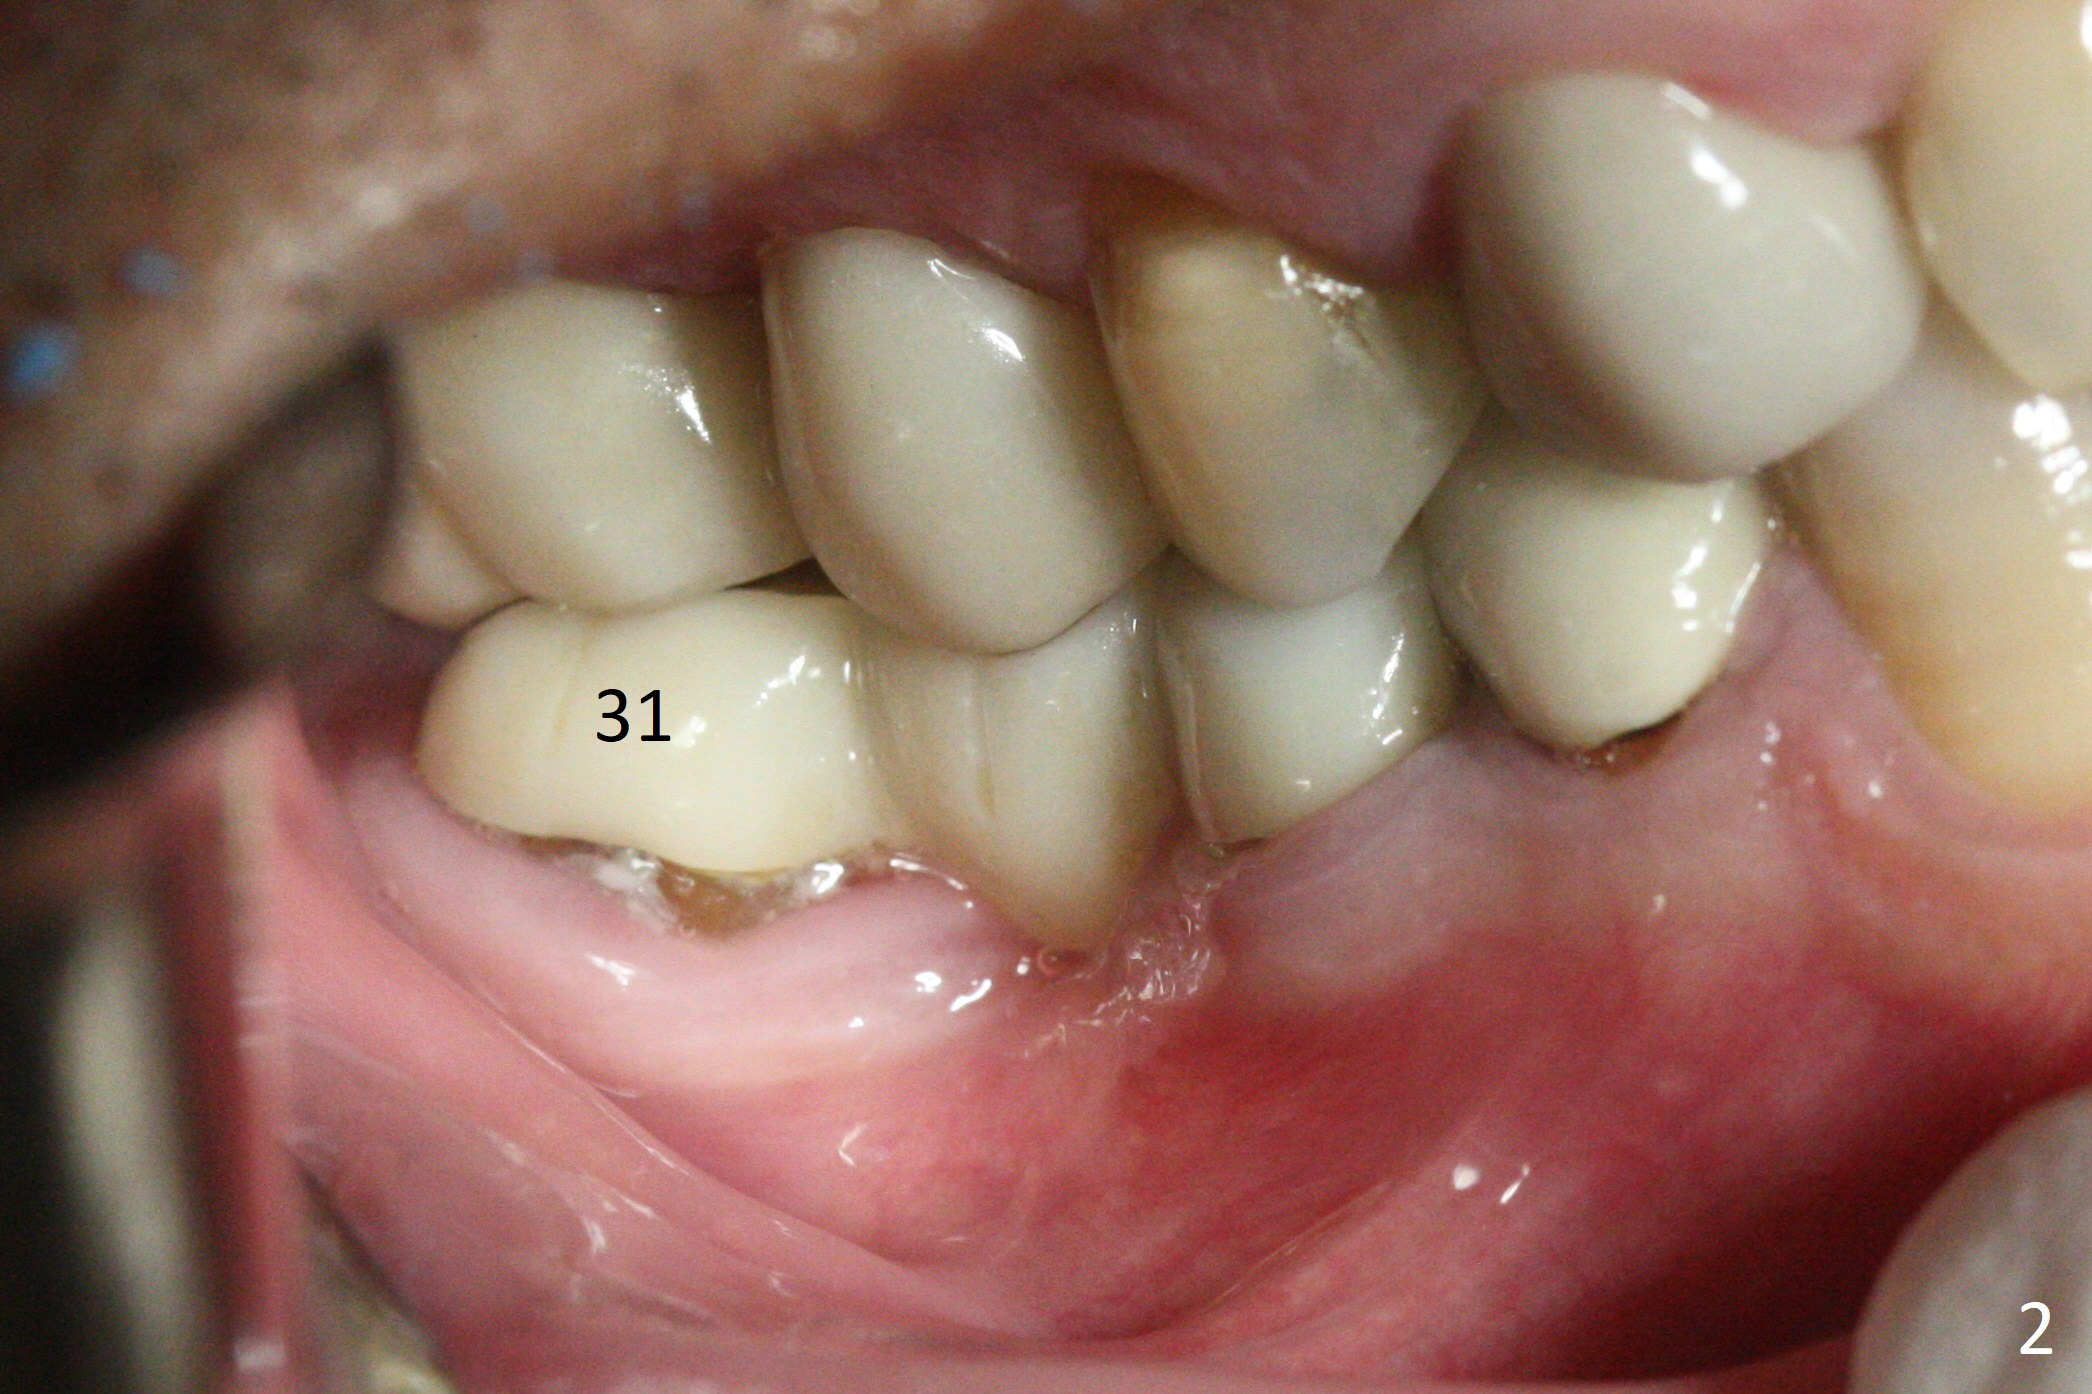

Preop examination shows that the buccal plate at #30 is atrophic (Fig.1 *). The mesiodistal width of the pontic is narrow as compared to the retainer at #31 (Fig.2). It appears that a narrow implant should be placed at #30 and should be able to sustain functional loading. After ridge reduction at #30 (Fig.3 ^) and extraction and debridement at #29, osteotomies at these sites are initiated with 1.2 mm and 2 mm drills, respectively. Probably due to low bone density, the osteotomy at #29 drops deep and close the Mental Loop (red dashed line). While the trajectory at #30 improves, the osteotomy at #29 remains close to the Mental Loop (Fig.4), asymptomatic with infiltration anesthesia. A 3x12(2) mm 1-piece implant is placed at #30 and 3.8x16 mm 2-piece implant at #29 (Fig.5,6 with insertion torque >50 and <50 Ncm, respectively). The large distal defect at #29 (Fig.3,5 *, most likely due to post-related perforation) is later filled with bone graft (data not shown). After placing an abutment at #29 and suturing, periodontal dressing is applied. Three months later, the meisal gap of #29 disappears while the distal one reduces (Fig.7 *). The abutment is changed to 4.5x4(4) mm one before reprep for impression. There is no bone loss 9 months post cementation (Fig.8) or 3 years 9 months post cementation (Fig.9). In fact the crown is lost at #31. At repeated request from the patient, a prefabricated post and crown will be fabricated for short term purpose while an implant is going to be placed at #19. The new crown at #31 has no occlusal contact (Fig.10), which may change over time.